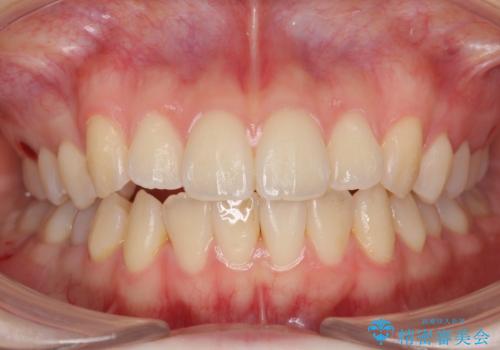

下の八重歯 歯を抜かずに インビザライン治療

抜歯してワイヤー矯正という選択肢も提案しましたが、マウスピース矯正で、歯を抜かずに並べてほしいとのことでした。

スペースを確保するために、歯をわずかに削る処置、奥歯を後ろに下げる処置(インプラント矯正)を行っています。

- 104.5万円(マウスピース矯正 93.5万円、矯正用スクリュー11万円)費用は治療当時の料金となります

途中患者様のご都合で治療を中断していたため、長くかかっていますが、実質2年程度で終わる内容でした。